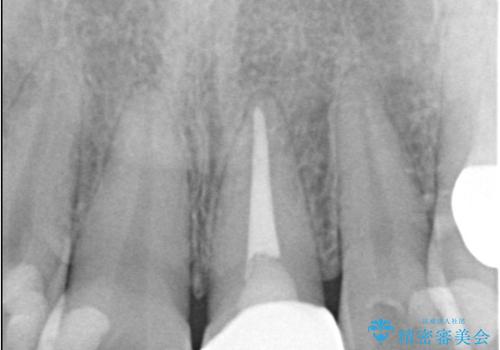

オールセラミッククラウンで治療を行い見た目の改善を行いました。

- 15万4千円(オールセラミッククランスペシャル14万3千円+仮歯1万1千円)費用は治療当時の料金となります

右上1もCRが入っており治療を勧めましたが、希望されず左上1のみ行いました。

色味は左上2に合わせたいとのご希望だったので、左上2に合わせています。